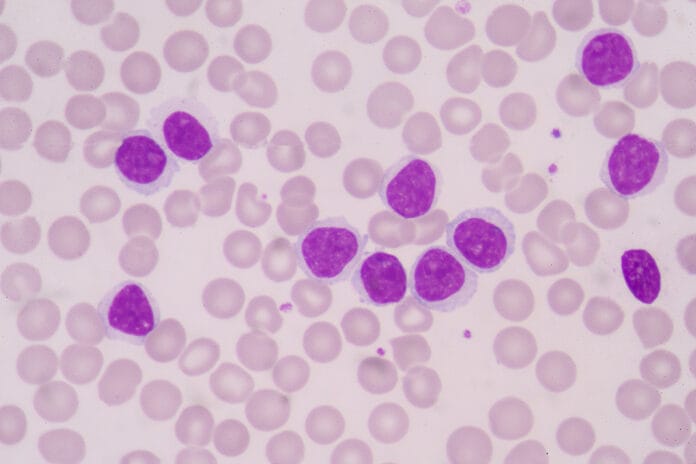

Oral Myeloid Sarcoma Lesions Linked to Acute Myeloid Leukemia

A study by the Journal of the American Dental Association recently explored how Oral Myeloid Sarcoma can manifest as gingival or mucosal swelling in certain patients....